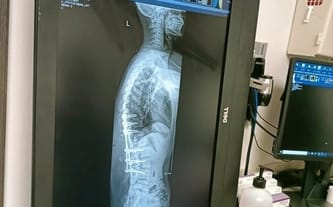

Aby stawiać pewne kroki, wspinać się po górach, pewnie prowadzić samochód i pokonywać wszystkie życiowe przeszkody muszę poddać się również operacji nogi, która ponad dziesięć lat temu zesztywniała, wskutek czego nie mogę jej zginać. Po krótkim czasie od tego wydarzenia zarówno w nodze, jak i pośladku zaczęły zanikać mięśnie. Kiedy pierwsza zbiórka organizowana przez Siepomaga osiągnęła swój cel, od razu wyznaczyliśmy termin operacji kręgosłupa.

Moja historia jest na tyle długa i zawiła, że naprawdę ciężko zmieścić ją w kilku akapitach. Niektóre sytuacje były dla mnie na tyle bolesne i traumatyczne, że moja głowa sama wypiera je z pamięci. Historię mojej choroby rozpocząć można od dnia narodzin, kiedy okazało się, że moja lewa noga jest dwa razy grubsza od prawej, a na moich plecach znajdują się trzy dużych rozmiarów guzy.

Okazały się one unerwioną i ukrwioną częścią organizmu, a z biegiem czasu mutowały i atakowały inne części mojego ciała – pośladek i nogę. Każdego dnia towarzyszył mi ogromny ból, a uczucie frustracji, wynikającej z tego, że żaden lekarz nie jest w stanie mi pomóc, albo chociaż określić co mi jest, rosło w dynamicznym tempie.

Moja historia jest na tyle długa i zawiła, że naprawdę ciężko zmieścić ją w kilku akapitach. Niektóre sytuacje były dla mnie na tyle bolesne i traumatyczne, że moja głowa sama wypiera je z pamięci. Historię mojej choroby rozpocząć można od dnia narodzin, kiedy okazało się, że moja lewa noga jest dwa razy grubsza od prawej, a na moich plecach znajdują się trzy dużych rozmiarów guzy. Okazały się one unerwioną i ukrwioną częścią organizmu, a z biegiem czasu mutowały i atakowały inne części mojego ciała – pośladek i nogę. Każdego dnia towarzyszył mi ogromny ból, a uczucie frustracji, wynikającej z tego, że żaden lekarz nie jest w stanie mi pomóc, albo chociaż określić co mi jest, rosło w dynamicznym tempie.